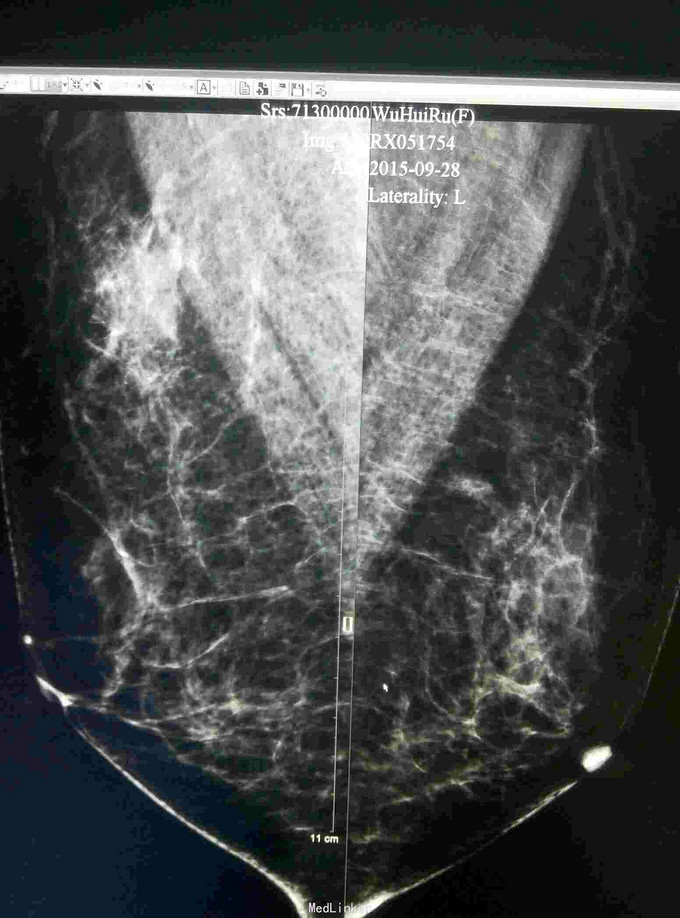

患者,女,50岁,体检发现右乳肿物1月

查体:体格检查未触及明显肿物 辅助检查:彩超钼靶如图所示

诊断:右乳纤维瘤? 治疗:局麻下行右乳肿物切除活检术,术后病理示:右乳肿物符合血管肉瘤样变。经汇报讨论,采取全乳切除加腋窝淋巴结清扫,术后可考虑放疗。